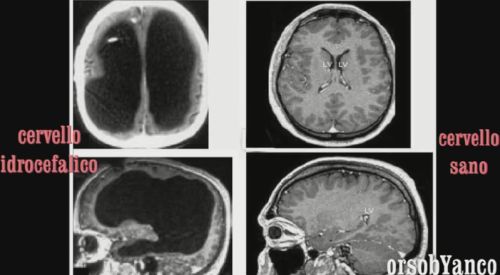

La verdadera adquisición de Consciencia está en la Mente, no en el cerebro, como se puede deducir fácilmente de algunos ejemplos flagrantes de personas descerebradas que tienen una Consciencia de sí mismo que, según la neurofisiología no debería existir.

Sergio Sala informa de un caso interesante de una mujer que, para algunos de los problemas relacionados con la falta de partes sustanciales del cerebro, parece haberlos compensado con otras partes del cerebro :

El extraño caso de Michelle, la mujer sin medio cerebro.

Varios periódicos han hablado recientemente sobre el caso de Michelle, de treinta años de Virginia, que tiene una vida casi normal a pesar de haber nacido sin la mitad del cerebro, la mitad izquierda. La historia, que sin duda es interesante, se ha propuesto como una demostración de la existencia de "plasticidad cerebral".

Por ejemplo, no ve lo que está a la derecha (porque no tiene centros visuales para analizar el campo visual derecho, que se encuentra precisamente a la izquierda) y la muñeca derecha es espástica. Además, se pierde con facilidad, no entiende el razonamiento abstracto y tiene una tendencia a asumir actitudes infantiles.

Pero Michelle habla sin atascos particulares, lee, va al cine, ve la televisión.